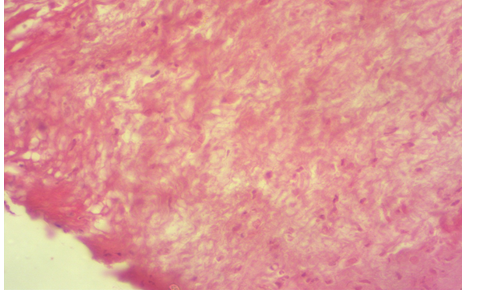

Photomicrography of control group at 30th days post operation showed new blood vessels, granulation of tissue invasion the area with the presence of active fibrosis (H&E 100X).